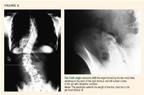

Congenital scoliosis may result from a range of anomalies in the developing vertebrae and most commonly presents as a left thoracic curve. The radiograph below shows a small left thoracolumbar curve due to a hemivertebra in a child with congenital scoliosis. A hemivertebra results from failure to form a complete vertebra, as opposed to a bar, which is failure of segmentation to form disk spaces between vertebrae. Two bars across the same vertebral segment form a block vertebrae with no potential for deformity. The greatest potential for deformity occurs when there is a hemivertebra on one side of the spine across from a bar.

These vertebral defectshemivertebra, bar, and blockusually occur during the first six weeks of gestation; they therefore coincide with organogenesis, which explains their common association with other conditions. Any left thoracic curve should therefore prompt a more thorough evaluation, including MRI and renal ultrasonography, to look for congenital vertebral anomalies or defects in other organ systems. Patients with congenital curves include those who have Klippel-Feil syndrome5,12 (Figure 7), Goldenhar syndrome5 (Figure 8), or Jarcho-Levin syndrome5 (Figure 9).